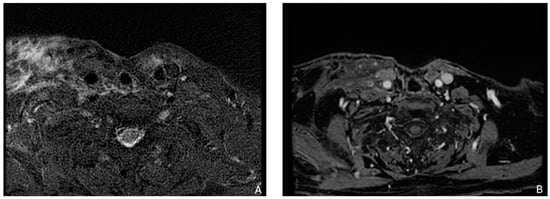

3.2.2. Radiomics Models